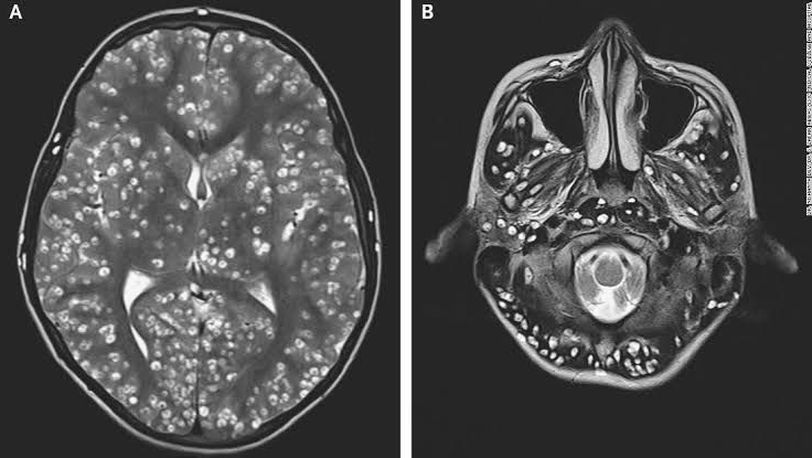

Neurocysticercosis is a preventable parasitic infection of the Central Nervous System, caused by Taenia Solium (pork tapeworm). The worm enters the body when undercooked pork is ingested or water containing the parasite is consumed. The larvae of pork tapeworm build up and continue to multiply in the brain, eyes as well as muscles. If not treated timely, it can develop into disseminated cysticercosis and can cause death. Below is a case of an 18-year-old male who came to the Emergency Department with generalized tonic-clonic seizures with a history of pain in the right inguinal region for the past 1 week. A general physical examination was conducted which concluded that the patient was confused with tenderness in the right-sided testis, accompanied by swelling around the right eye. MRI head was done immediately, which showed multiple cystic lesions with well-defined borders. All the areas of the brain were involved, including the cerebral cortex, brainstem, and cerebellum. Ultrasonography of the right eye and right testis also showed innumerable cystic nodules. All the findings suggested a diagnosis of disseminated cysticercosis which was later confirmed by Western Blot and ELIZA. Due to the high cyst burden, antiparasitic medications were not administered as it can worsen the inflammation and intensify the cerebral edema. Moreover, increased inflammation with ocular lesions can cause permanent loss of vision. Antiepileptic medications and dexamethasone were administered but unfortunately, the patient died after 2 weeks.